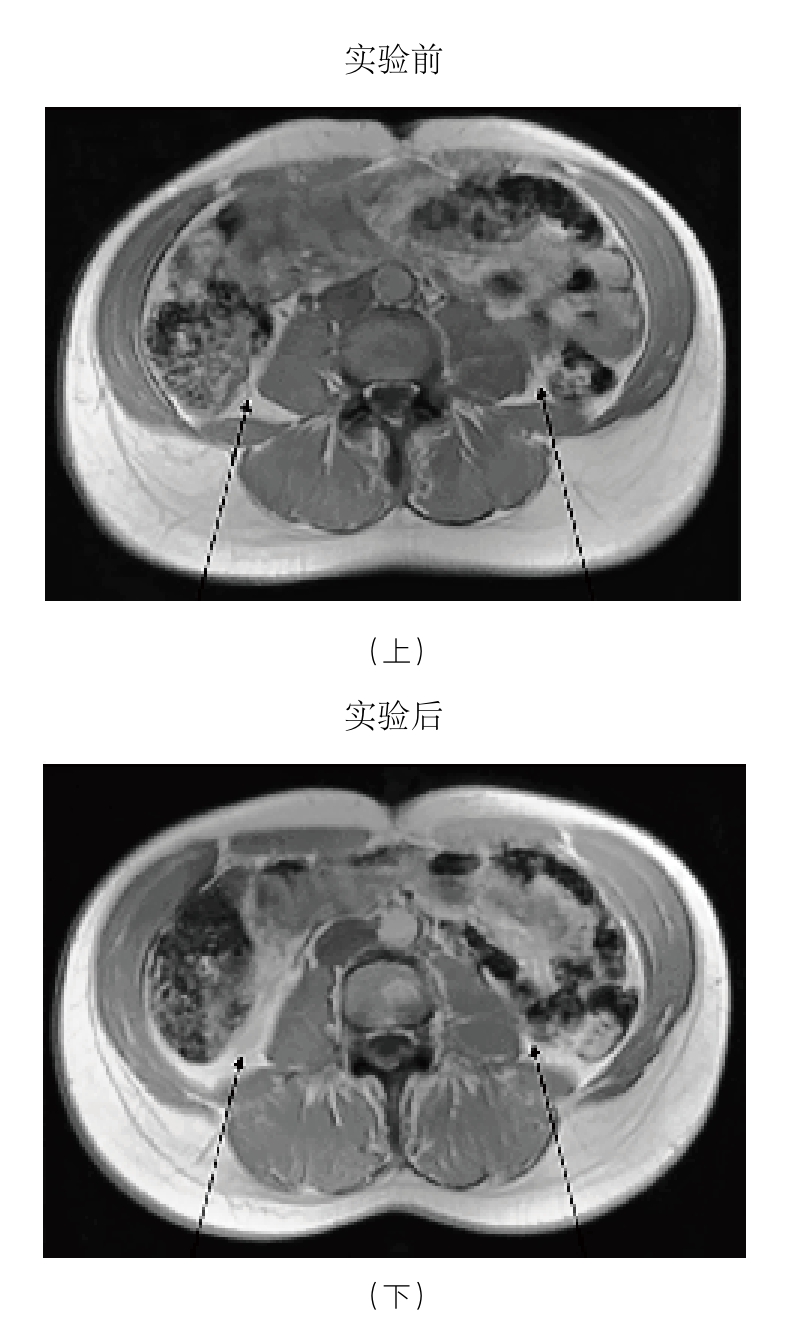

过多的脂肪,尤其是内脏内部和周围的脂肪会引发慢性轻度炎症。这是久坐引发慢性轻度炎症的第一种方式,这一过程的机理提醒我们,久坐会带来危险,而原因很可能仅仅就是这一行为造成了体重的增加。有一个事实值得反复强调,那就是坐在舒适的椅子上时,肌肉几乎不承受任何压力。而即使是蹲着或者跪着也需要肌肉参与,哪怕只是站着,每小时都会多消耗8大卡能量,像把洗好的衣物叠起来这种轻量活动每小时要比坐着多消耗100大卡能量。 36 这些能量累积起来的效应不可低估。对于我而言,每天花5小时仅仅从事一些哪怕是非锻炼类的低强度身体活动,所消耗的能量就相当于跑步一小时。所以,如果我坐着而没有活动,那么我午饭摄入的热量就很有可能转化成了脂肪,而不是被燃烧掉。丹麦的研究人员付费招募了一组健康的年轻人,让他们像名副其实的“沙发土豆”那样,每天走动不超过1 500步(约1.6千米),持续时间为两周。这项实验的结果或许有一些警示作用。研究人员对实验前后被试的腹部进行了扫描,对比结果显示,这些男性被试的内脏脂肪在两周内增加了7%(见图3-2下图)。 37 更加令人不安的是,这些被试在脂肪增加的同时,还开始表现出慢性轻度炎症的典型症状,其中包括分解餐后血糖的能力降低。需要说明的是,这个实验只是对久坐的间接后果进行研究。当然,这并不是说久坐是造成这些丹麦年轻人变胖的唯一原因。身体长时间不活动外加热量摄入过多,共同造成了过多内脏脂肪的堆积,继而点燃了慢性轻度炎症的“星星之火”。还有一个现象,那就是这些志愿者增加的脂肪大部分是内脏脂肪,这说明他们一直处于压力之下。我们还知道有很多缺乏活动的人其实体重并没有超重,却饱受慢性轻度炎症的困扰。那么,久坐还会通过哪些方式诱发慢性轻度炎症呢?

图3-2 男性被试实验前后的腹部磁共振成像扫描对比图

注:实验前(上图)和经过两周久坐或进行极轻量活动后(下图)。被试的内脏脂肪(箭头所示)在两周内增加了7%。

资料来源:Olsen,R. H.,et al.(2000),Metabolic responses to reduced daily steps in healthy nonexercising men, Journal of the American Medical Association 299: 1261-63. Bente Klarlund Pedersen提供。